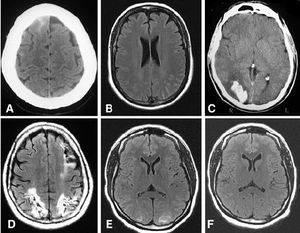

Figure 2: Example of brain Computed tomography ([1])

Diagnostic radiology, the imaging modalities using ionizing radiation, produces images of anatomical internal structures of human organs and physiological (functional) biological systems and helps significantly improve patient management and care in screening and diagnosis, assessing treatment response, predicting prognosis, and detecting disease recurrence. Modern diagnostic radiology assures faster, more precise diagnosis and enables monitoring of a large proportion of diseases. It has been estimated that in about one half of all cases, radiological procedures (conventional radiography, fluoroscopy, computed tomography) have a substantial impact on the speed of diagnosis and in a large fraction of cases they are of decisive importance in guiding patient management and therapy.

In diagnostic radiology, x rays, produced by machines, are transmitted through the patient’s body and detected by a receptor (or detection) system to generate the required image of the organs under investigation. The differential absorption of x rays in tissues and organs, owing to their atomic composition, is the basis for the various imaging methods used in diagnostic radiology. Modern diagnostic radiology uses a digital process for image acquisition, transfer, process and storage. Over the past years, with the tremendous technological progress and collaborative efforts in radiation protection, the radiation doses used in diagnostic radiology have been significantly reduced and continue to be reduced through technological innovations especially in CT (ICRP Publication 135 Diagnostic Reference Levels in Medical Imaging; ICRP Publication 121 Radiological Protection in Paediatric Diagnostic and Interventional Radiology; ICRP Publication 105 Radiological Protection in Medicine; ICRP Publication 93 Managing Patient Dose in Digital Radiology).

Diagnostic radiology are mainly applied in the areas: (1) Digital general radiology (DR); (2) Mammography; (3) Fluoroscopy systems; (4) Mobile radiography and fluoroscopy; (5) Bone density scan (DXA); (6) Computed tomography (CT); (7) Conventional tomography and tomosynthesis; (8) Dental radiography / CBCT; (9) Nuclear medicine including hybrid imaging (SPECT/CT, PET/CT, PET/MRI); (10) Cardiology; (11) Neuroradiology; and (12) Paediatrics.